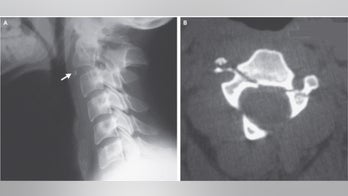

May 22, 2017 Man survives 'hangman's fracture' after crash A young man in Tunisia who was in a high-speed crash suffered a broken neck — in an injury doctors call a "hangman's fracture" — yet recovered with no lingering problems, according to a recent report of the man's case.